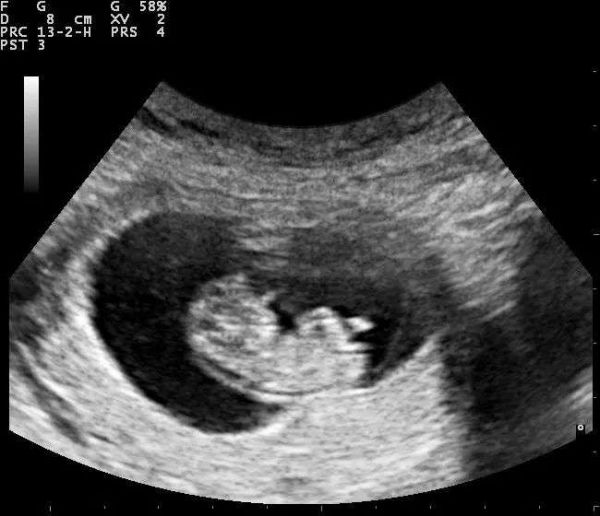

这种凝胶的正式名称是超声耦合剂,它的主要用途正如它的名字,是用来“耦合”的媒介。超声检查用人耳听不到的超声波(频率大于20千赫)扫描人体,并把回声信号转换成体内的图像信息。B超呈现的是不同亮度 (Brightness) 的黑白图像,而彩超则是在此基础上以彩色呈现组织的血流情况。

超声图像显示的早期胎儿 | 图源:Wikimeidia Commons